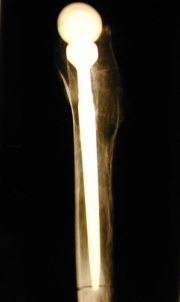

Bleibt diese Osseointegration über Jahre bestehen? Die folgenden Bilder illustrieren dies. Abb. 15a und b zeigen das Präparatröntgen einer 83-jährigen Patientin, welche 20,7 Jahre nach Implantation des Titaniumschaftes verstorben ist. Es finden sich stabile Verhältnisse. Die Abbildungen c und d zeigen, dass das Implantat (Ti) stabil im umgebenden Knochen verankert ist (Dünnschliffpräparate Prof. Dr. F. Lintner, Pathologie, Otto-Wagner-Spital). Dies bedeutet, dass die Osseointegration auch beim alten und sehr alten Menschen funktioniert.

Abb. 15a                                                                                                  Abb. 15b